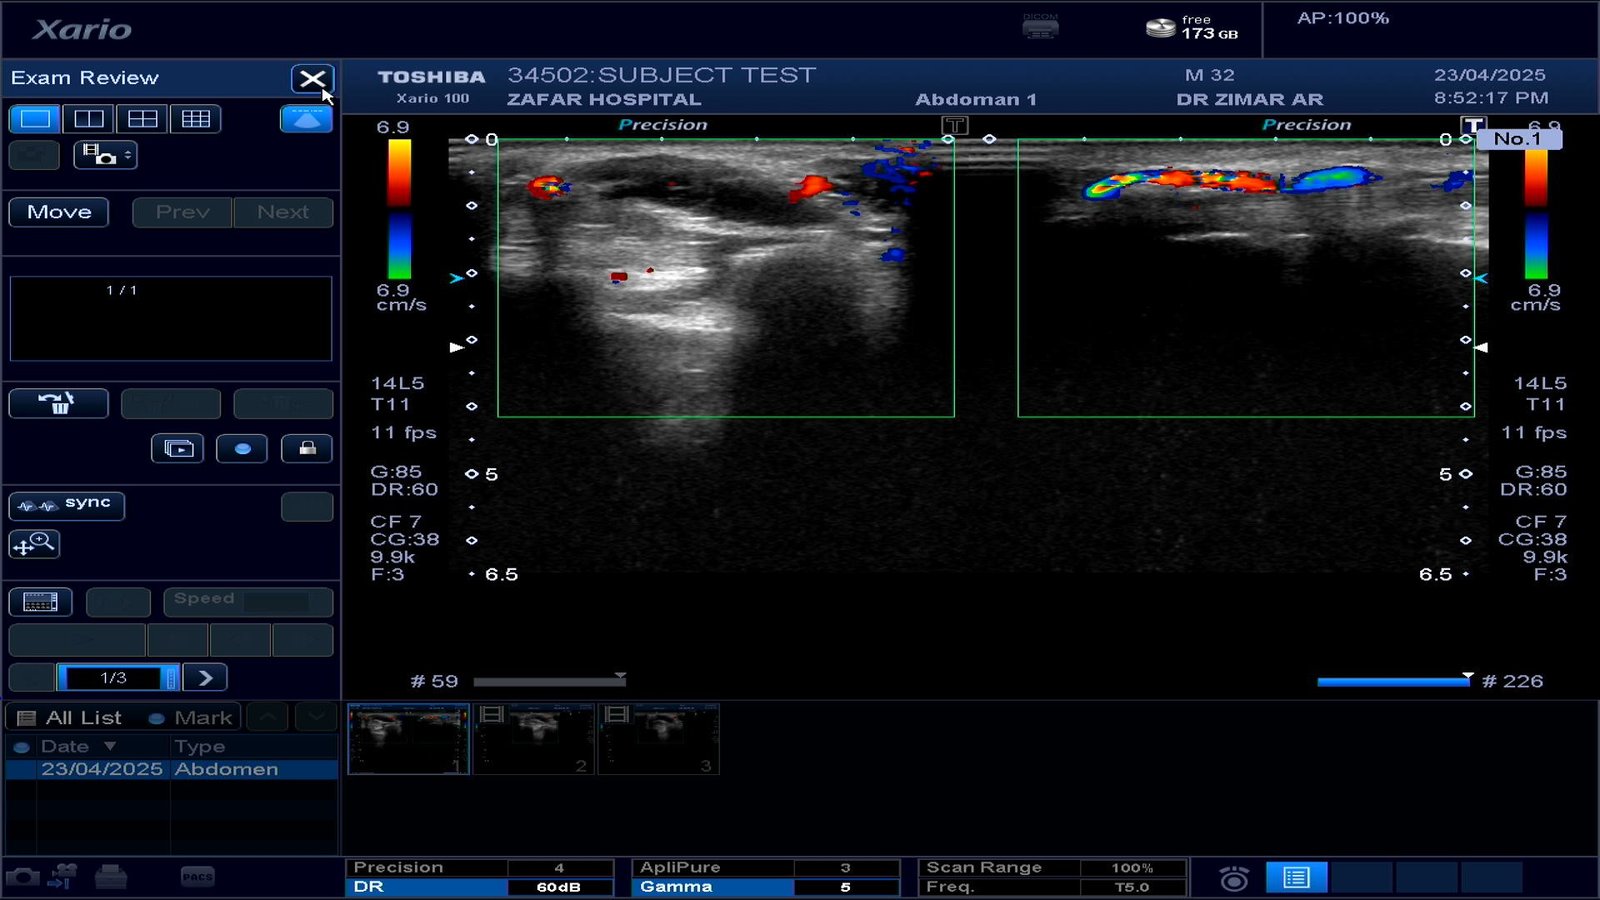

We provide guidance for implementation of our PACS server into respective Radiology modalities including MRI, CT, X-Rays and Ultrasound. For machines without activated DICOM nodes, studies can be sent to us via dedicated password protected links after retrieval from the machines.